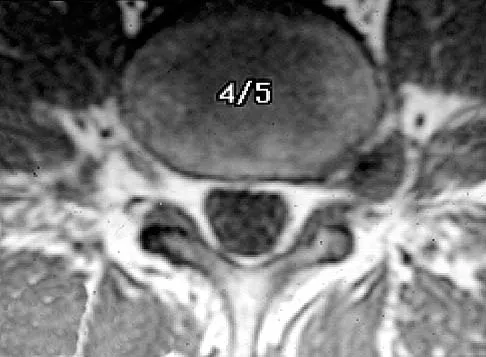

A radiograph, MRI scans, and a biopsy specimen of a 9-year-old boy with thigh pain are shown in Figures 37a through 37d. Management should consist of

Explanation